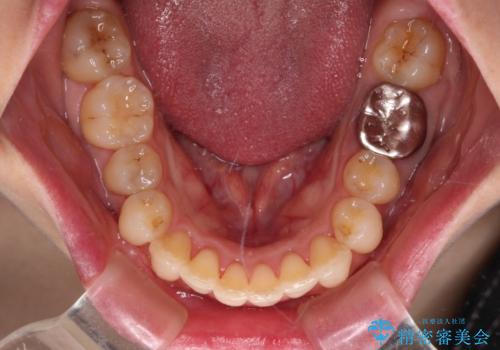

- 上下の前歯のデコボコを気にして来院された患者様です。

妊娠中であり、途中通院が難しくなる可能性があることから、インビザラインによる矯正治療を行うこととしました。

上下顎歯列全体の後方移動とIPR(歯と歯の間を削る)によってデコボコが解消するように設計しました。